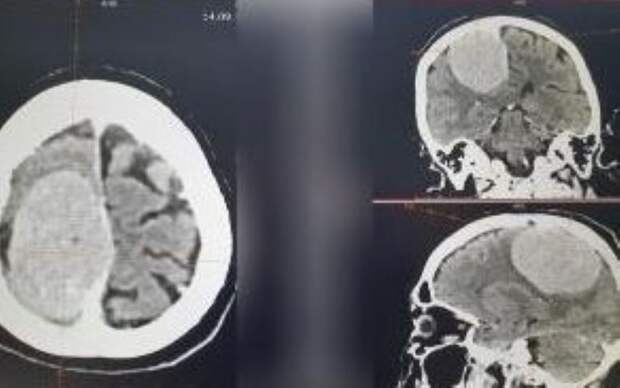

Новый медицинский успех – в Орловской областной клинической больнице благополучно завершилась сложная операция по удалению опухоли в головном мозге. Огромное новообразование, размером почти с треть головы, отравляло жизнь 74-летней пациентки. Пенсионерка поступила в нейрохирургическое отделение с парасагиттальной менингиомой в правой теменной области.

– Операция проводилась по экстренным показаниям. Была выполнена костно-пластическая трепанация черепа с последующим микрохирургическим удалением опухоли головного мозга, – сообщается на портале области. Операцию проводило пять человек. Всё завершилось благополучно. Пациентку уже выписали из больницы с положительной динамикой. Впереди долгий процесс реабилитации.